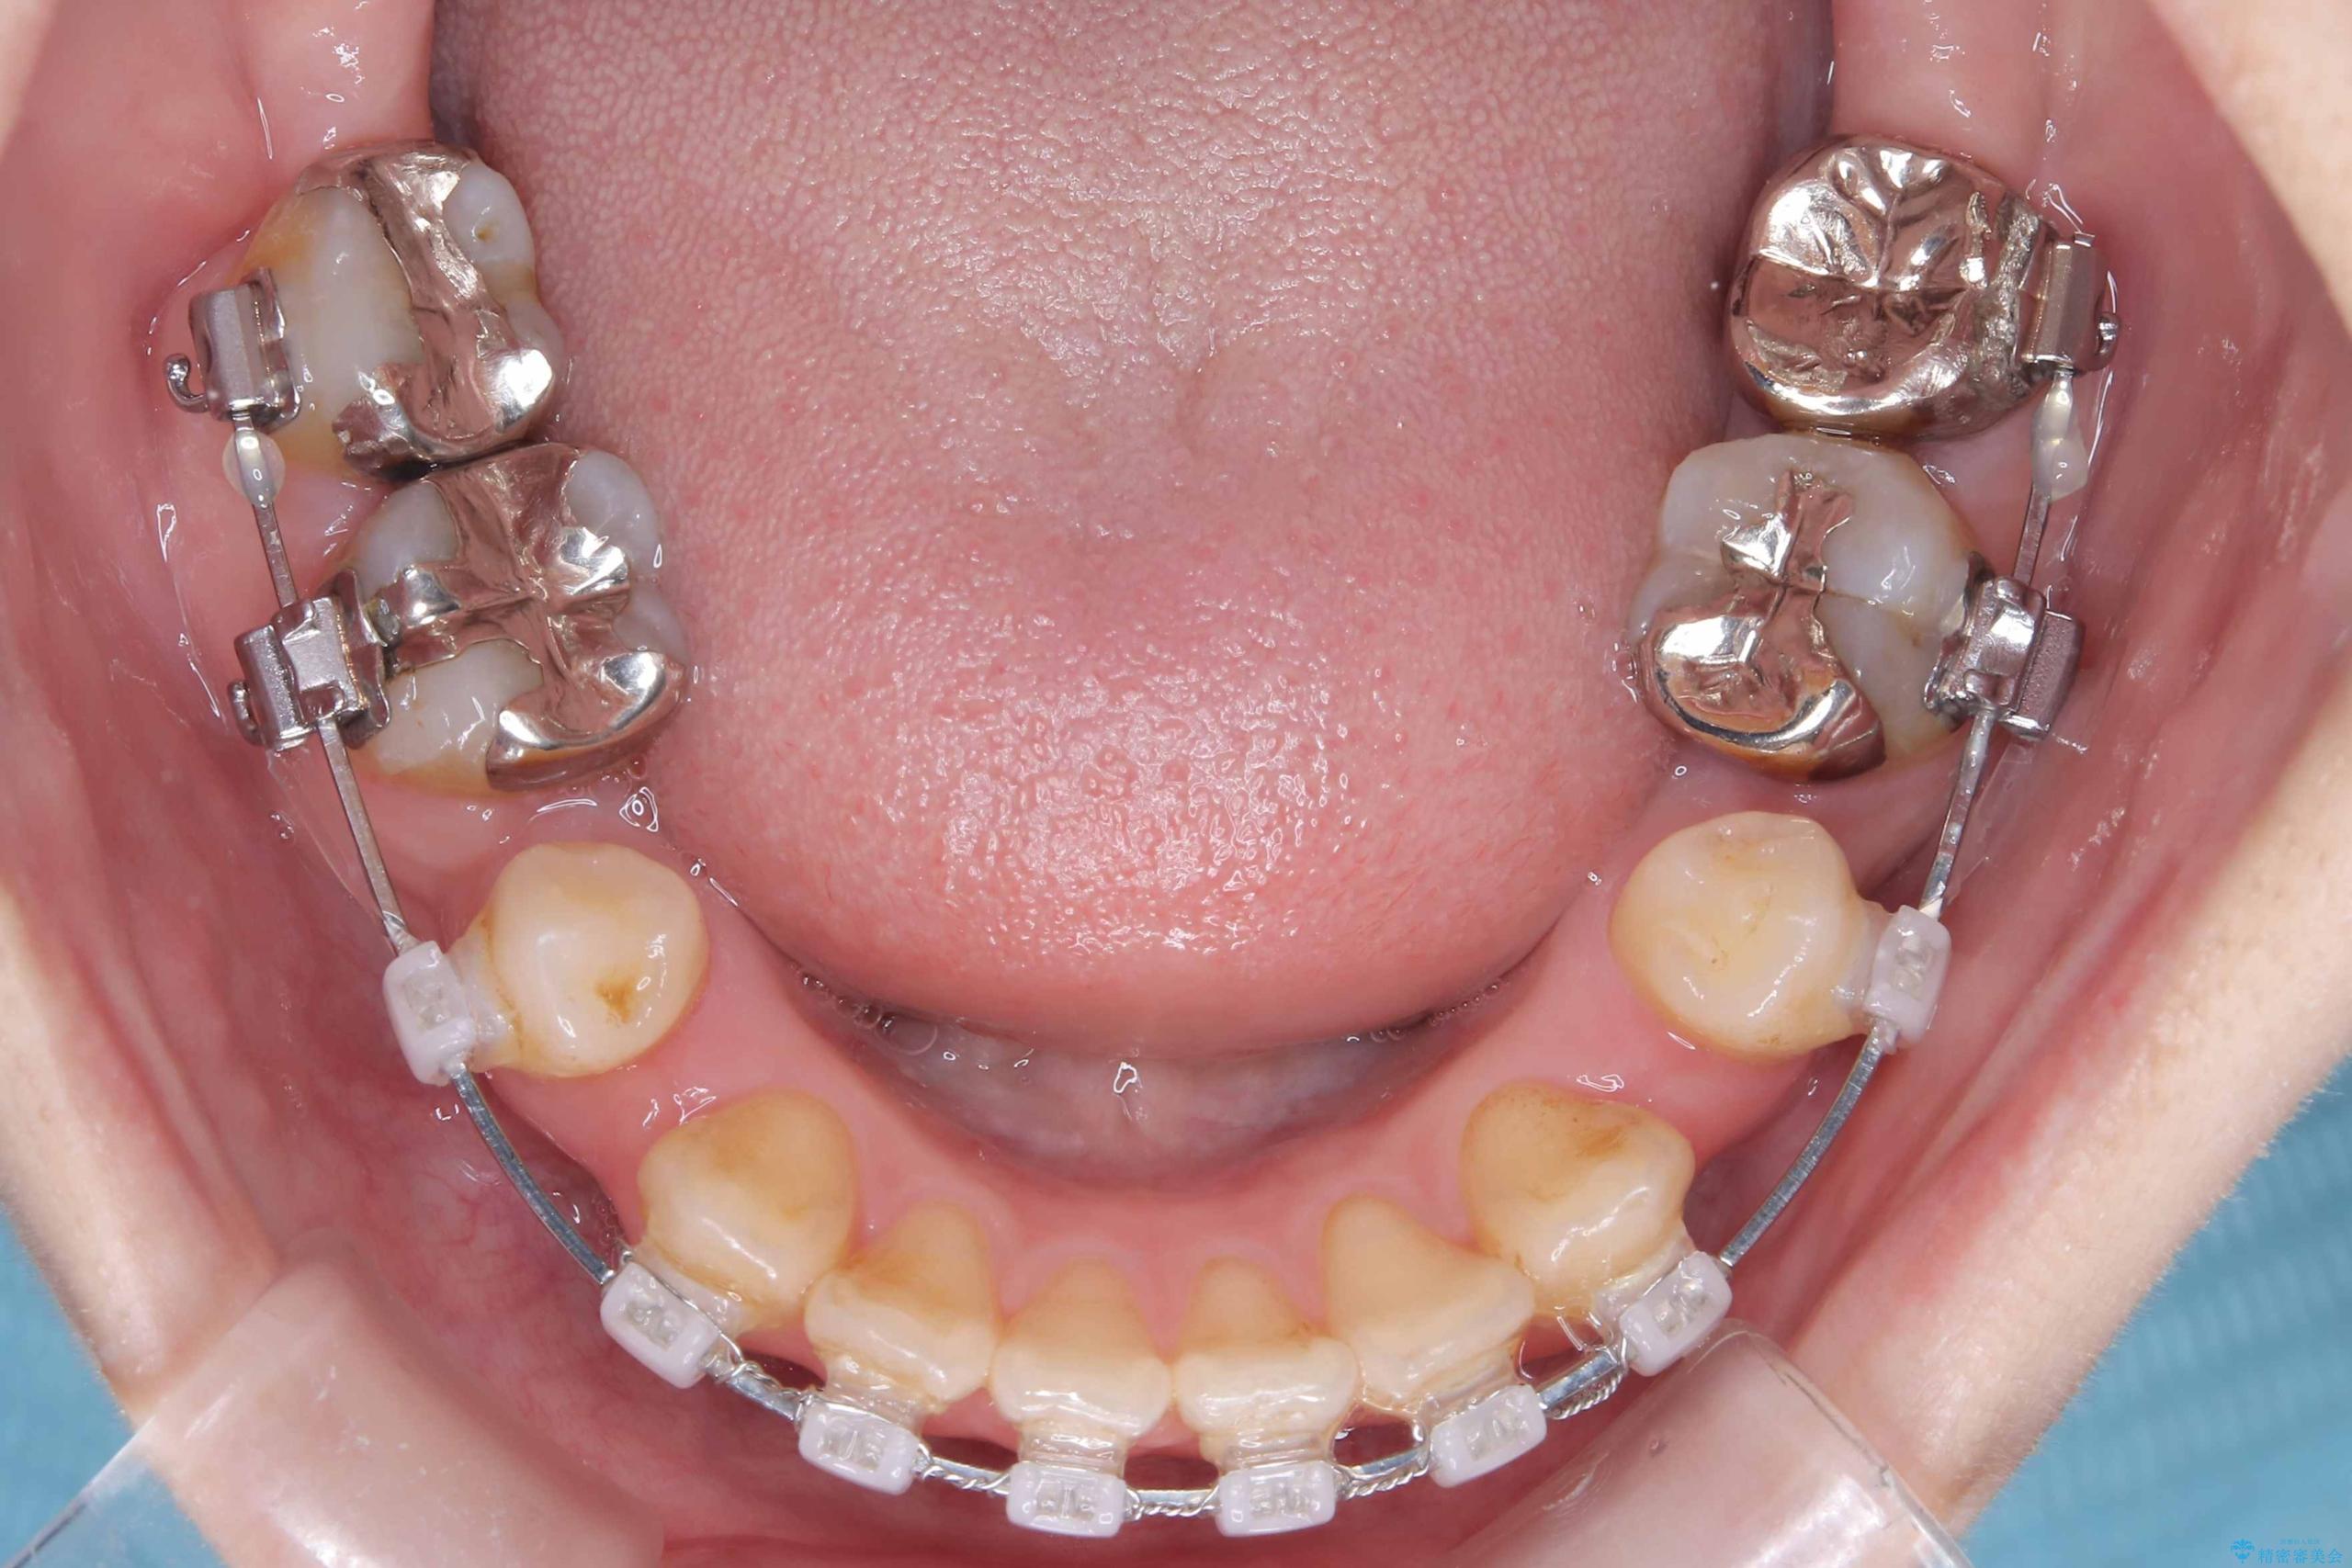

- ワイヤー矯正(クリア装置)

- 開咬と歯のデコボコ(叢生)、八重歯を主訴にご来院された患者様です。

矯正の精密検査の結果、上顎左右4番および下顎左右5番の計4本を抜歯し、ワイヤー矯正(クリア装置)にて治療を行いました。